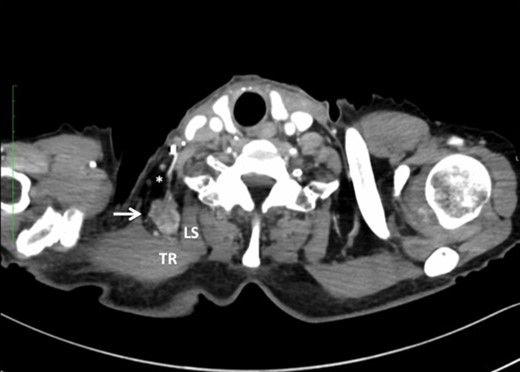

Undifferentiated carcinoma was confirmed by excisional biopsy of the tumor located between TR and LS (arrow).

Another possible explanation is blood-borne spread rather than lymphatic spread. Toh et al. [5] reported isolated right ANM in esophageal adenocarcinoma with no prior evidence of nodal disease. They insisted that right ANM could be caused by blood-borne spread instead of lymphatic spread based on anatomical considerations; however, it is difficult to confirm whether isolated LNM as seen in case 3 is caused by skip metastasis via bypassed lymphatic flow or blood-borne spread manifested as systemic disease.